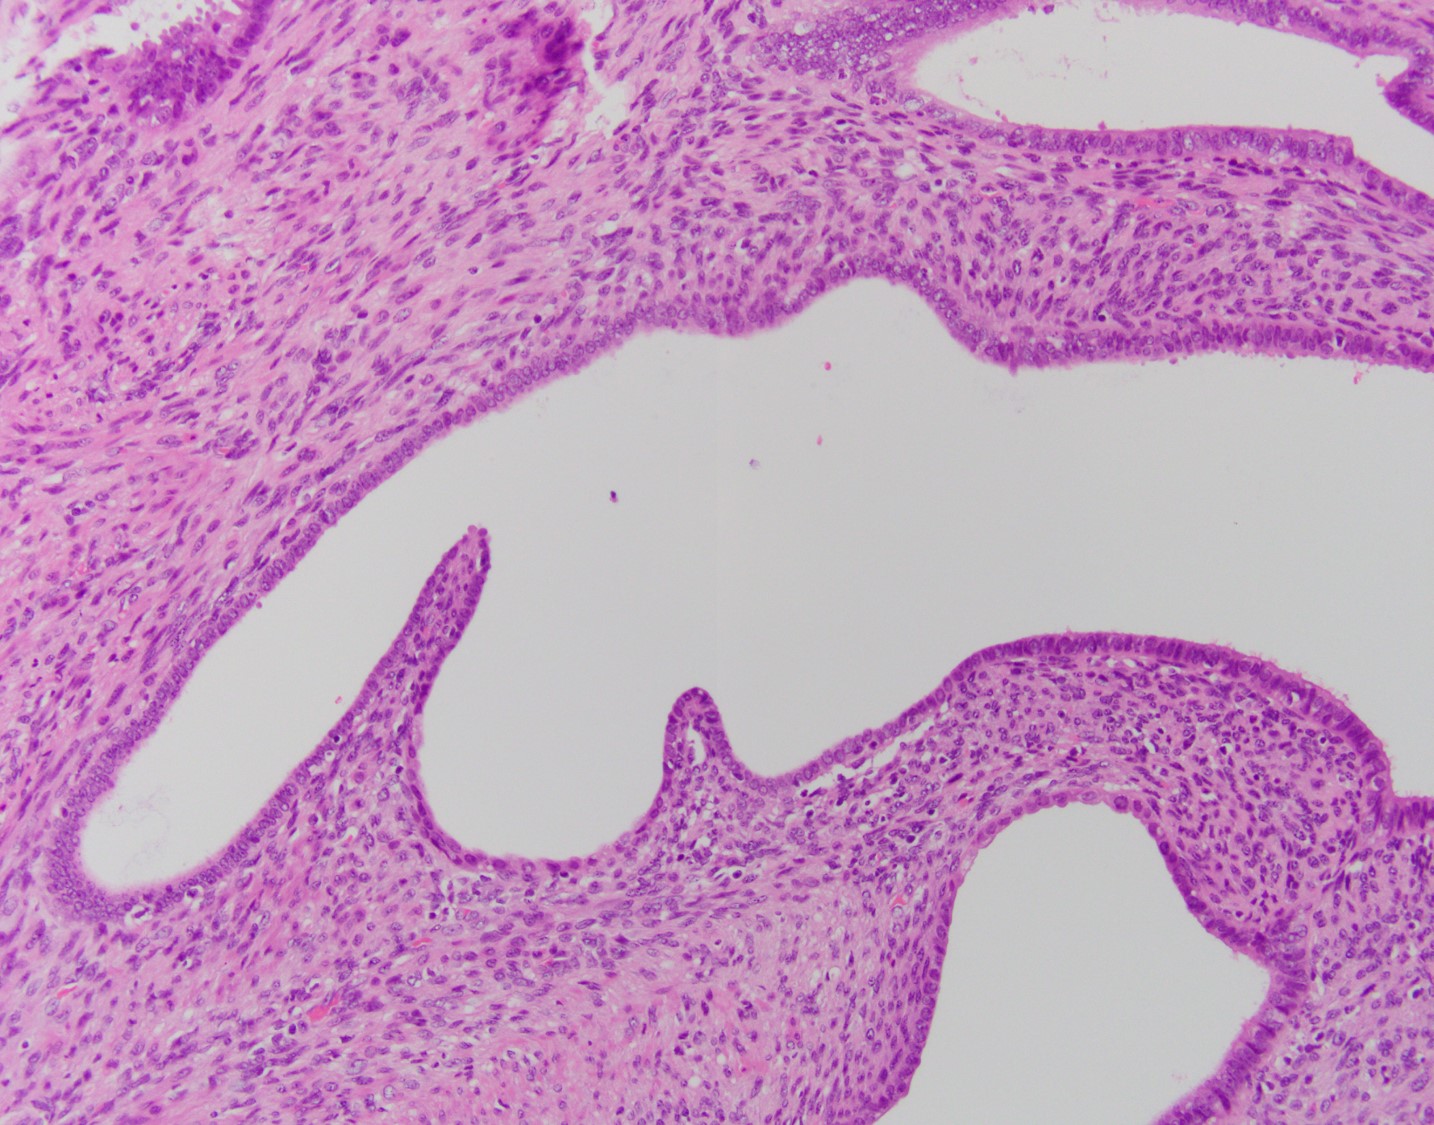

Histologically, MA usually have a phyllodes-type pattern with dilated glands lined by benign endometrial or ciliated epithelium surrounded by a distinct cuff of neoplastic stroma. This stroma is normally hypercellularand can have subtle atypical features. These tumors are often positive for CD10, ER, and PR, however there have been a subset of cases that are negative for CD10.

There are two components comprising this specimen, which are focally intimately associated with one another. The first component consists of endometrial glands and stroma surrounded by smooth muscle bundles, which in the proper clinical setting could represent a benign adenomyomatous polyp. The second component consists of a biphasic process of benign glands and stroma with a phyllodes-like architecture. The stroma surrounding the glands shows periglandular "cuffing" with very low-grade atypia. There is increased mitotic activity (greater than 2 mitoses/10 HPF) in the areas with the phyllodes-like architecture. Immunohistochemical staining showed two distinct staining patterns in the two components. The adenomyomatous polyp component showed CD10 highlighting endometrial stroma in the adenomyomatous areas with surrounding smooth muscle bundles positive for caldesmon and desmin while the stroma in the phyllodes-like area was positive for desmin and caldesmon but was negative for CD10. The patient was treated with a hysterectomy, where there was minimal focal residual disease identified.